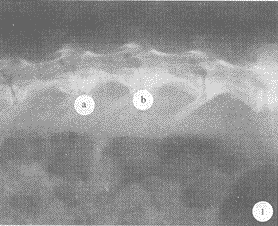

术后4周,空白组椎间隙清晰,无密度改变;UDB植入椎间隙密度相对降低,呈现轻度吸收;DBM植入和BMG植入椎间隙密度无明显改变(图1)。术后8周,空白组仅椎体边缘有少许模糊阴影;UDB植入椎间隙密度明显降低,移植块呈明显吸收;DBM和BMG植入椎间隙中央均有不同程度密度增高,但以后者为明显。术后12周,空白组无明显变化;UDB植入移植物已基本吸收;DBM植入椎间隙密度增高略低于椎体,其面积为椎间隙的2/5;BMG植入椎间隙完全融合,椎间密度近于或高于椎体(图2)。

图1 术后4周兔腰椎X线片 DBM植入(a)和BMG植入(b)椎间隙密度无明显改变

, 百拇医药 Fig. 1 Rabbit lumbar X-ray,4 weeks after operation

There was no obvious difference in the densities of

intervertebral space of DBM group(a) and BMG group(b)